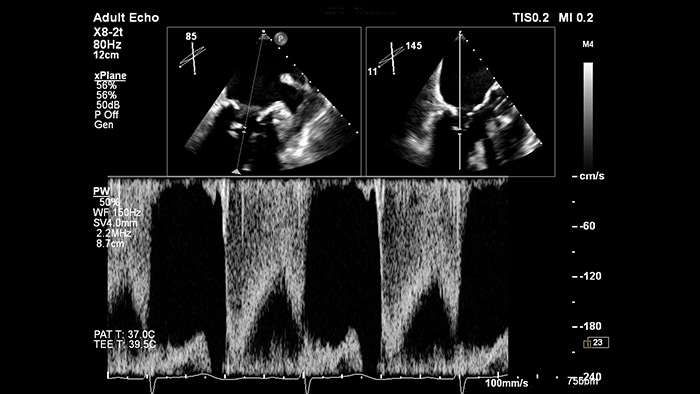

Уверенность в правильном расположении строба при оценке сердечного кровообращения с опцией xPlane Doppler